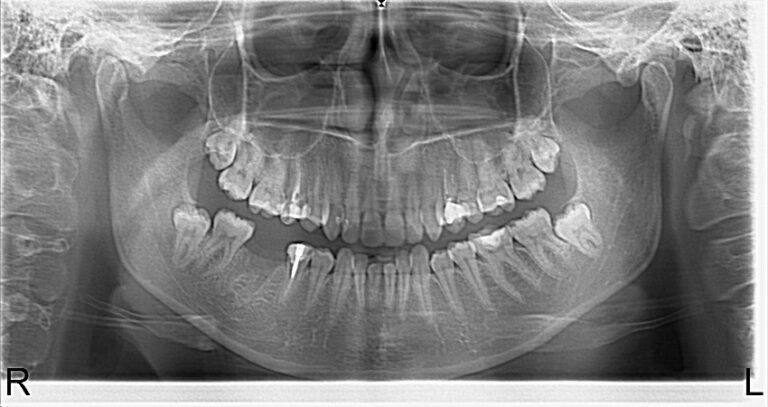

Photo 1.Panoramic roentgenogram of a 46-year-old patient A. before treatment.

Photo 2.Panoramic roentgenogram of the patient after extraction of her 46th tooth and osteoplasty.